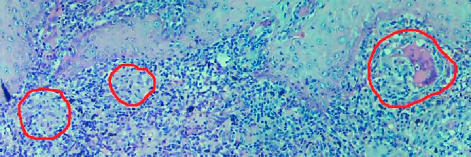

Leishmaniasis background and histology presentation. The World Health Organization (WHO) has selected cutaneous leishmaniasis as a neglected tropical disease (NTD) with growing, uncontrolled, and ignored infection affecting millions of people every year [14, 9]. It is unfortunately one of the world’s most neglected poverty-related diseases, affecting the poorest people in developing countries and it is associated with risk factors like malnutrition, immune system deficiency, migration, inadequate education, illiteracy, gender inequality, and a shortage of services [1]. Furthermore, only eight countries in the world contribute to 90% of leishmaniasis cases: Afghanistan, Algeria, Brazil, Iran, Pakistan, Peru, Saudi Arabia, and Syria [12]. It is a vector-borne infection caused by the protozoan parasite Leishmania. The vector is the female sand-fly. The lesions of cutaneous leishmaniasis vary in presentation ranging from a single self-limited skin lesion to multiple large destructive and ulcerated lesions on mostly the exposed parts of the body such as face, forearms, and lower legs [2]. Skin biopsy is considered the gold standard method for confirmation of diagnosis. The presence of large epitheloid granulomas and small hematoxylinophilic LD bodies (that are round, uniform in appearance, intracytoplasmic and sometimes distributed around the outer rim of the vacuoles) is critical for diagnosis and confirmation of leishmaniasis [4]. Large granulomas are visible at 10X but the smaller hematoxylinophilic bodies (around 3-4mm in size) are usually visible at 40X and can easily be missed if they are few in number, leading to misdiagnosis. Specialized dermatopathologists are the only ones who can diagnose these accurately based on patient history, clinical features, and laboratory diagnosis. It is thus critical to share the digitized slides of these cases from rural poor remote areas with dermatopathologists (mostly residing in urban centers) for quick diagnosis and accurate management of the patient.

We demonstrate our WSI creation workflow on Leishmaniasis cases, as shown in Figures 1 and 4. An expert pathologist reviewed the cases and annotated granulomas as well as LD bodies on the stitched images and our generated images in Figure 4. To show generalizability of our approach, we also show results on core biopsies of breast, duodenum, stomach, liver, and lymph nodes (Figure 5).